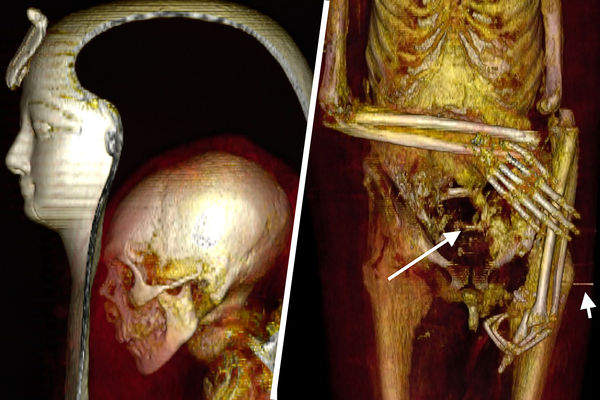

Мумию египетского фараона Аменхотепа впервые смогли рассмотреть египетские ученые с помощью компьютерной томографии. Удалось выяснить, что фараон был обрезан, его рост составлял 168,5 см, на момент смерти Аменхотепу было 35 лет. Спустя несколько веков после захоронения в его гробницу наведались грабители и в поисках сокровищ поломали мумии кости, но бальзамировщики сделали все возможное, чтобы восстановить тело. Исследователи надеются, что в будущем удастся подобным образом, не разматывая бинтов и не снимая масок, рассмотреть мумии и других правителей Египта, узнав больше об их анатомии, возможных болезнях и причинах смерти.

Исследователи обнаружили у Аменхотепа множество травм, но все они оказались посмертными: переломы шеи и позвоночника, вывихи и переломы рук, перелом лобковой кости. На одной из рук отсутствуют два пальца, они уложены в районе живота мумии. По всей видимости, мумия пострадала от рук расхитителей гробниц.

В бинтах исследователи также обнаружили около 30 украшений, в частности пояс из металлических (вероятно, золотых) бусин в задней части тазовой области, и фаянсовый амулет в форме раковины улитки у левого бедра.

При повторном захоронении мумию явно пытались «отремонтировать» — пропитанные смолой бинты фиксировали оторвавшуюся из-за перелома шейных позвонков голову, прикрывали повреждения брюшной полости. Сломанным и вывихнутым конечностям придано подходящее положение. Ступни зафиксированы с помощью деревянных дощечек.